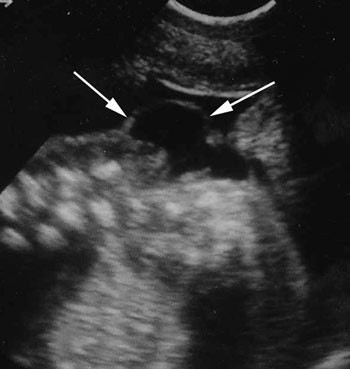

I august 1986 var det duka for samling av om lag hundre ekspertar frå ulike fagområde, vesentleg frå medisin, som frå ulike innfallsvinklar skulle drøfte bruk av ultralyd på gravide. 27. – 29. august 1986 vart det nokre intense dagar med ultralyddebatt i Oslo. På halvannan dag skulle panelet (og andre) høyre 21 korte innlegg. Den faglege breidda som tilskiparane hadde lagt vekt på, kom ikkje heilt til uttrykk i dei inviterte innlegga. Med få unnatak var innleiarane medisinarar; ikkje ein gong jordmødrene var representerte her. Den første dagen vart det stadfesta kor langt organisering og bruk av ultralyd allereie var komen. Ei fersk undersøking viste at minst 43 avdelingar, som stod for over 68 % av fødslane, praktiserte screening. Sjølv på avdelingar som dreiv med berre indikasjonsbaserte undersøkingar, var det berre 14 % av pasientane som ikkje var blitt undersøkte med ultralyd. Dette gav eit gjennomsnittleg tal på undersøkingar per svangerskap på heile 2,45 (16). Panelet skulle altså ta stilling ikkje berre til praksis for framtida, men til ein praksis som allereie var godt etablert (fig 1) (17).

Større merksemd kring misdanningsproblematikken ville også ha komplisert det prioriterte screeningspørsmålet. I ein artikkel i Tidsskriftet like før konferansen hadde åtte legar frå Rikshospitalet presentert 14 tilfelle av fostermalformasjonar diagnostisert med ultralyd. «I den pågående debatt om ultralydscreening står spørsmålet om tidlig diagnostikk av misdannelser sentralt. I dette materialet ble kun to tilfeller diagnostisert før 30. uke,» skreiv legane, og meinte at det som lét seg diagnostisere før 20. veke først og fremst var anencephalus, tidleg utvikla hydrocephalus og større meningomyeloceler: «Andre misdannelser kan først diagnostiseres senere i graviditeten. Dette er ett av flere argumenter for rutinemessig ultralydundersøkelse også ved ca. 32 svangerskapsuker,» skreiv dei (21). På dette tidspunktet hadde ultralydlaboratoriet i Trondheim allereie fått medieomtale for å ha diagnostisert og behandla fleire foster yngre enn 30 veker (1, kap. 7). At misdanningsproblematikk ville vere eit argument for ultralydundersøking også i veke 32, kan vere ein grunn til at dette emnet vart tona ned under konferansen. For alle var samde om at den viktigaste ultralydundersøkinga ville vere om lag i veke 18, og spenninga var stor til om konsensuspanelet ville tilrå rutineultralyd i det heile. Mangelen på etikkdiskusjon ser med andre ord ikkje ut til å ha handle om at teknologien var for dårleg til å diagnostisere misdanningar, men snarare eit medvite val basert på ei klår motvilje mot å ta etikk/misdanningsproblematikk opp til brei drøfting. Desse problemstillingane vart nedprioriterte til fordel for andre spørsmål knytt til screening.